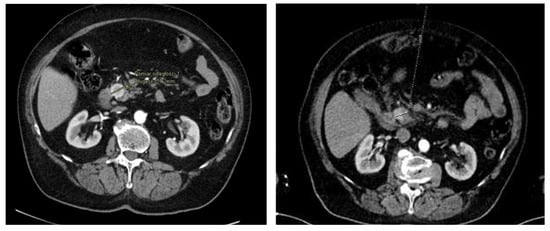

2. First Case